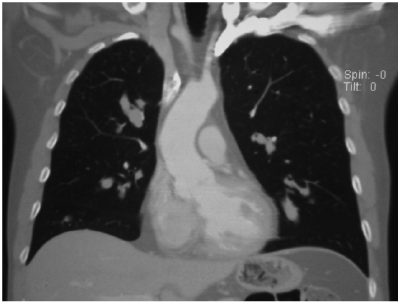

A 42-year-old male comes to your office after a bout of hemoptysis 2 days prior that he said was “concerning.”